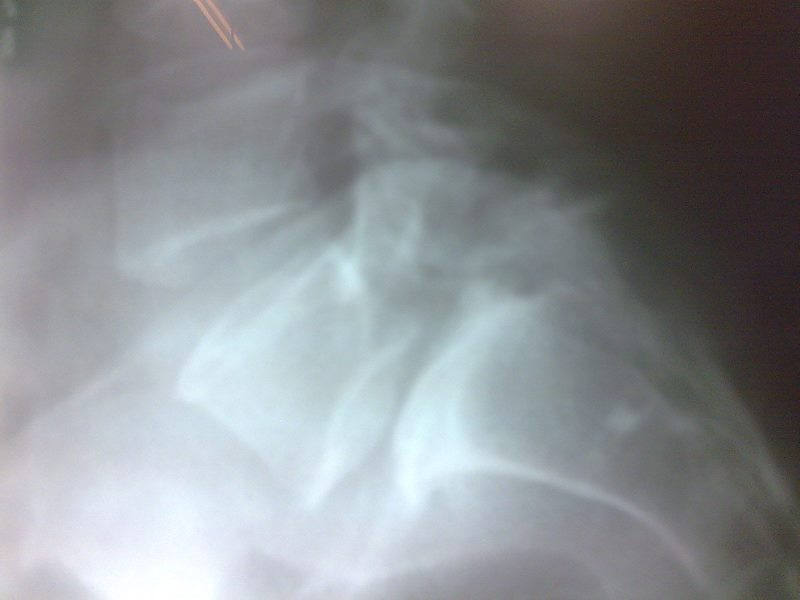

Radiografías con enfoque en fisiatría

Envíado por Dr. Hernán Darío Sánchez Ramos